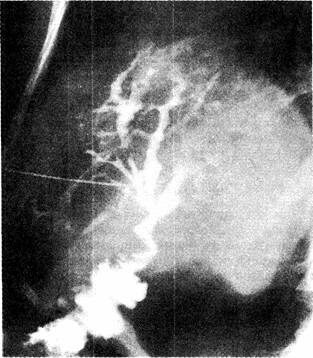

Фотографии и изображения, связанные с симптомами первичного склерозирующего холангита